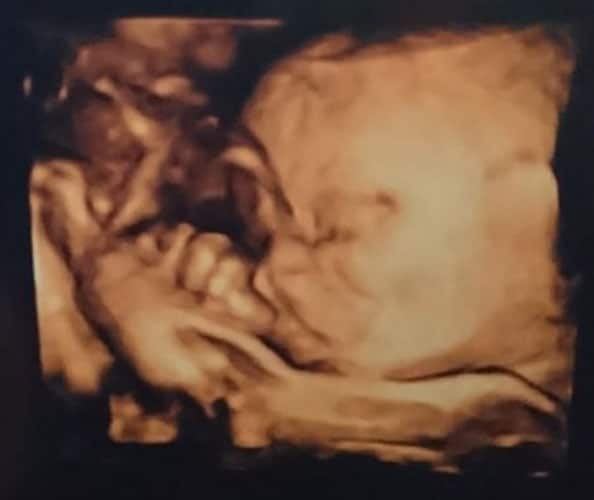

Ultraschallbilder aus dem 3. Trimester (29. bis 40. SSW)

Im dritten Trimester der Schwangerschaft ist das Baby so groß, dass es nicht mehr komplett auf ein Ultraschallbild passt. Nun kann man wunderbare 3D-Ultraschalle des Gesichts machen. In diesem Semester nehmen die Babys nochmal rasant zu und wer Glück hat, kann auf seinem Ultraschall schon erste Gesichtszüge erkennen.

Wer sich jedoch erhofft Gesichtszüge zu erkennen, der wird oft enttäuscht. Zwar kann man beim 3D-Ultraschall schon eine Menge sehen, aber das umgebende Fruchtwasser sorgt in den allermeisten Fällen für starke Störungen.